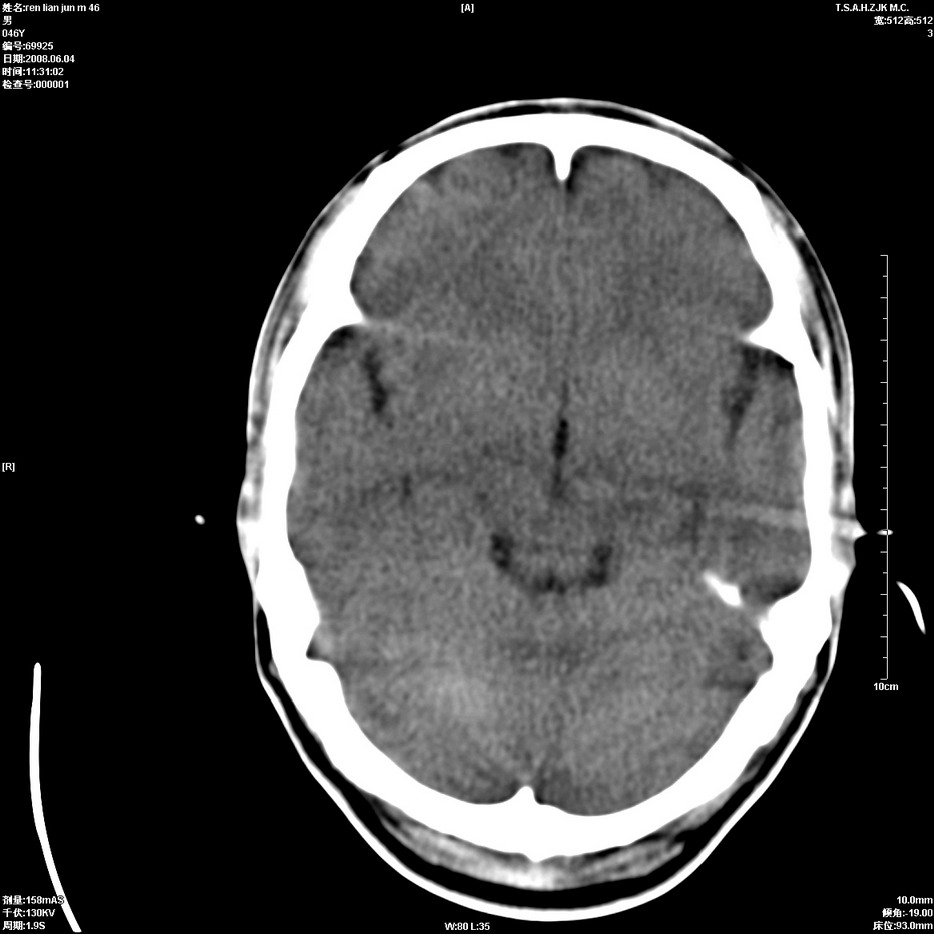

以下是引用qiu999在2008-6-5 17:14:00的发言:[br]考虑右肺中心型肺癌.颅内应做增强检查.

以下是引用形影不离在2008-6-5 19:18:00的发言:[br]右肺中心型肺癌并纵隔及左侧腋窝淋巴结转移,颅内应做增强检查。

以下是引用杀毒软件在2008-6-5 18:33:00的发言:[br]支持考虑右肺中心型肺癌,颅内病变是不是转移,不好说